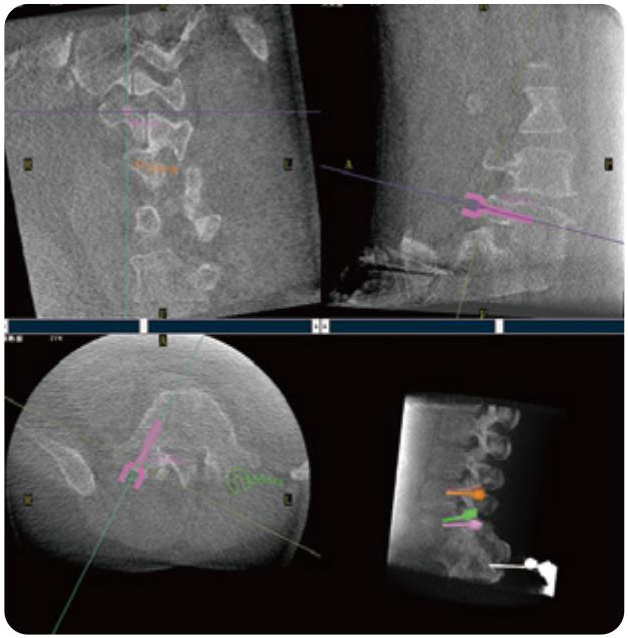

PL300B可應(yīng)用于多節(jié)段脊柱外科手術(shù),輔助醫(yī)生定位病灶部位,為脊柱外科手術(shù)(經(jīng)皮椎體成形術(shù)、椎弓根螺釘內(nèi)固定術(shù)等術(shù)式)提供術(shù)前手術(shù)流程規(guī)劃、入釘位置、角度可視化引導(dǎo),模擬仿真入釘輔助。